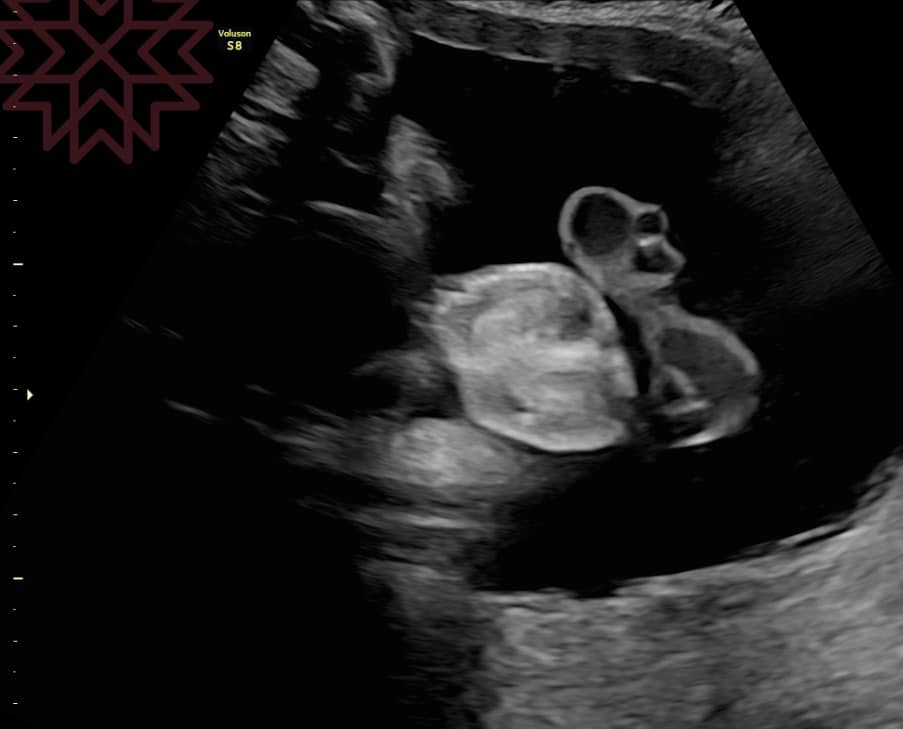

前幾天在門診中有媽咪問這個問題

可以呀

不過太早看不到

一般要28週以後才可以看得到

(就在圖片中

(你看到了嗎?

男寶寶的睾丸通常在懷孕大約28到32週之間從腹腔下降到陰囊

在這個過程中

睾丸會通過腹股溝管

最終到達陰囊